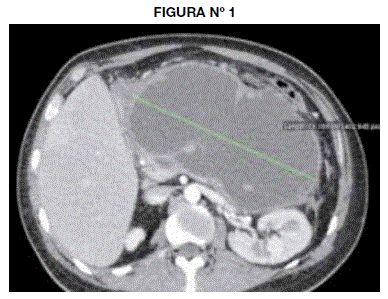

En la tomografía se observa una colección líquida multilobulada de aspecto homogéneo (10.8 UH) y baja densidad, de 2795cc de volumen calculado (19.18 X 19.55 X14.33cm) localizada en el saco menor (entre la pared posterior del cuerpo gástrico y el páncreas) y con extensiones a los espacios gastro-esplénico y subfrénico izquierdo contactando la fascia pararrenal anterior. Tiene paredes definidas con espesor máximo de 4.8mm.(Fig 1, Fig 2).